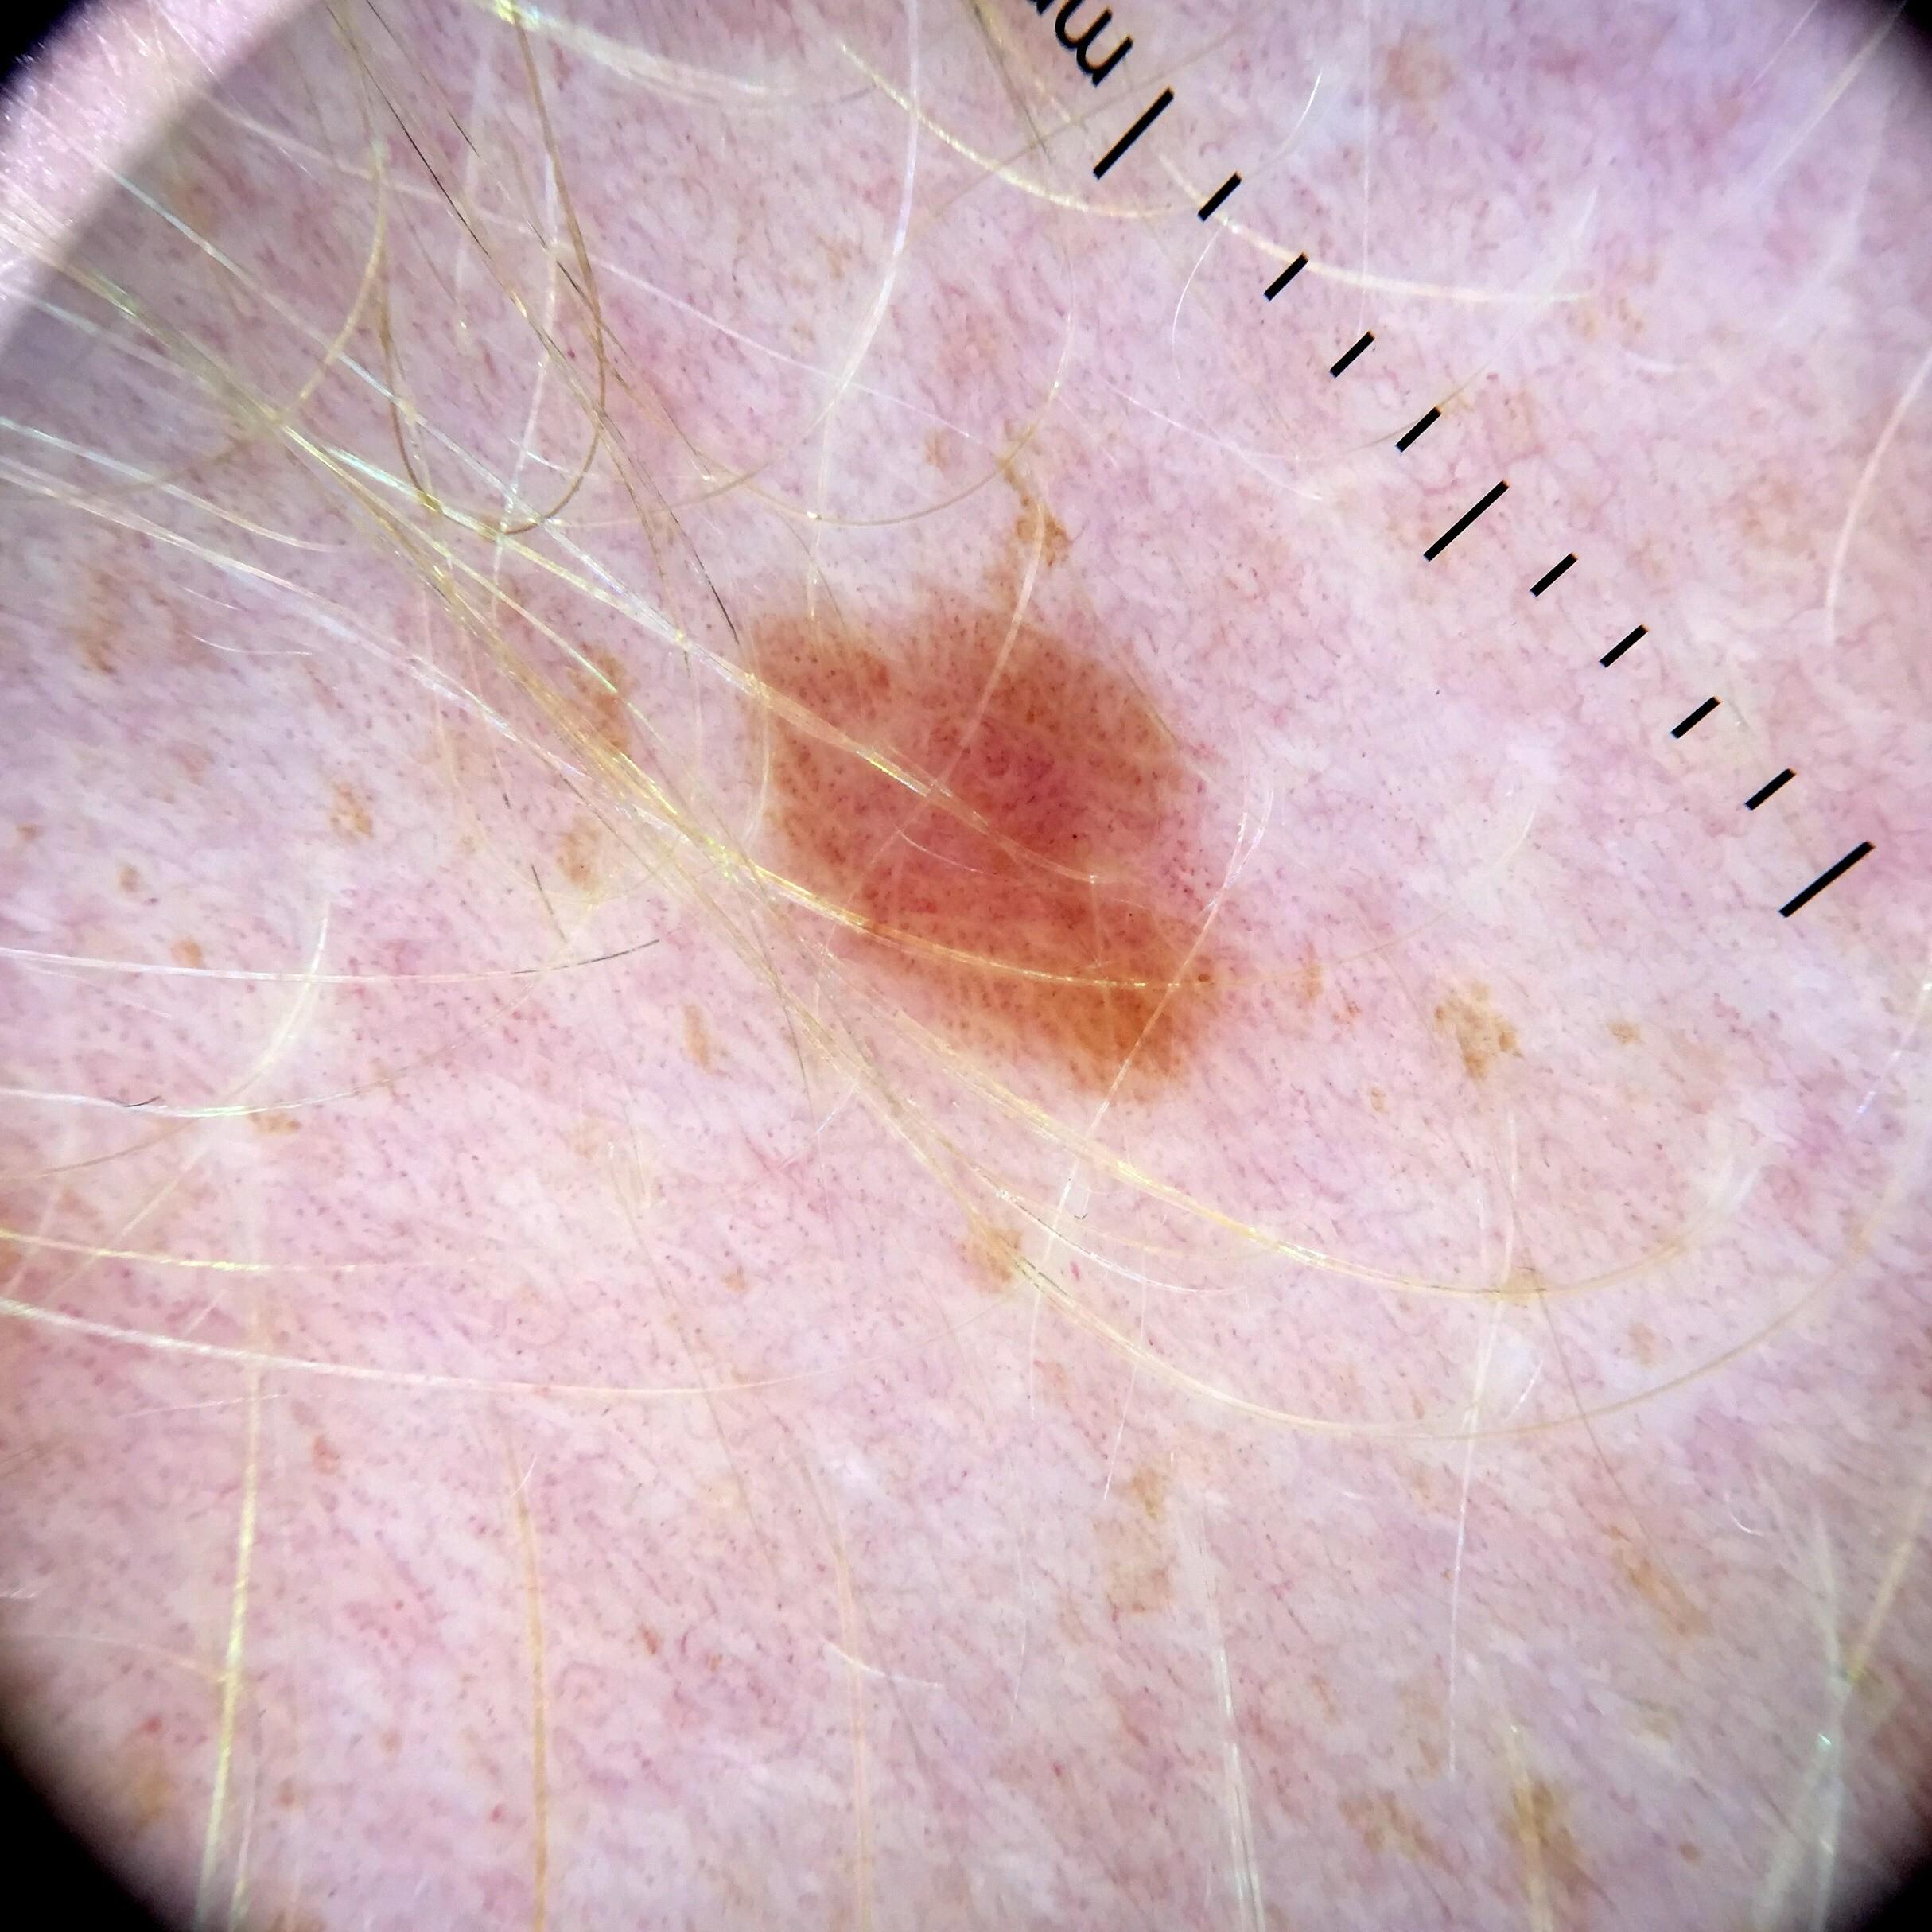

Field Value

acquisition_day 107

age_approx 40

anatom_site_1 Lower extremity

anatom_site_general lower extremity

concomitant_biopsy False

diagnosis_1 Benign

diagnosis_confirm_type single image expert consensus

family_hx_mm False

image_manipulation instrument only

image_type dermoscopic

lesion_id IL_1588126

patient_id IP_9794531

personal_hx_mm True

sex male